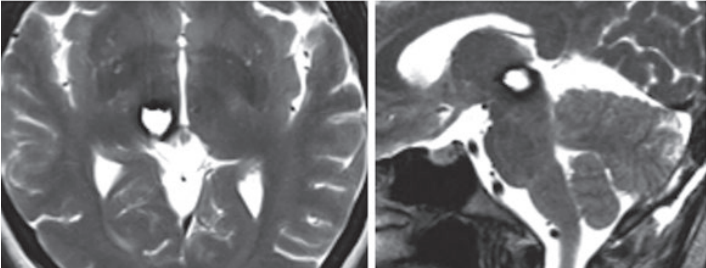

在手術(shù)切除腦海綿狀血管瘤的前3年,35歲Helen一次出現(xiàn)左手和左側(cè)面部的暫時(shí)性感覺(jué)障礙。1 年后出現(xiàn)二次具有類似癥狀的臨床發(fā)作。手術(shù)前三個(gè)月,再次出現(xiàn)左手和左側(cè)面部的暫時(shí)性感覺(jué)障礙,且癥狀惡化,咨詢INC國(guó)際神經(jīng)外科顧問(wèn)團(tuán)WANG成員、國(guó)際神經(jīng)外科聯(lián)合會(huì)WFNS主席巴特朗菲教授為其手術(shù)。軸向 (圖1a) 和矢狀平面 (圖1b) 的術(shù)前磁共振成像 (MRI) 顯示中腦上部和丘腦右側(cè)枕部有出血性海綿狀血管瘤。

圖1:術(shù)前mri